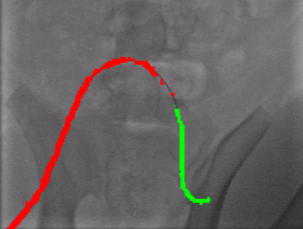

These functions are non-zero only within the interval , ensuring local control of the curve, which means that changes in a control point affect only the portion of the curve within this interval. Additionally, the constraint for all within the internal knots , normalizes the basis functions. To represent the guidewire, the parameter represents the normalized arc length along the guidewire, providing a smooth and continuous model of the guidewire’s geometry. Fig. 5 shows the B-spline guidewire representation.

We trained our network, SplineFormer, on the annotated dataset described in Section III. The model was trained for 300 epochs using the Adam optimizer with an initial learning rate of . The results, presented in Fig. 7, illustrate that SplineFormer successfully predicts the overall shape of the guidewire within a compressed feature space. While SplineFormer is not explicitly designed for segmentation, it demonstrates a strong ability to detect key points of the guidewire, particularly near the tip. In contrast, traditional segmentation models such as U-Net [40] generate qualitative masks but fail to capture the guidewire’s detailed geometry, often missing the tip due to low contrast. Consequently, U-Net’s segmentation outputs tend to be discontinuous and provide insufficient visual guidance for stable autonomous endovascular navigation.